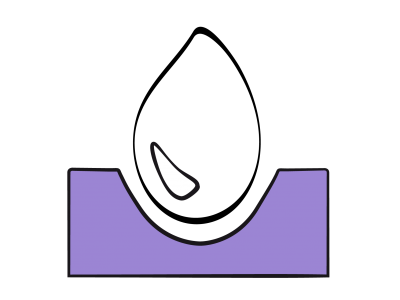

Il n'existe aucune mesure directe de la volémie utilisable en clinique. On se réfère habituellement à la détermination de valeurs de substitution, telles la pression artérielle ou la pression veineuse centrale (PVC). Or la pression et le volume de remplissage sont reliés entre eux par la compliance de la cavité cardiaque. Cette relation est curvilinéaire : les variations de pression (ΔP) sont minimes par rapport aux variations de volume (ΔV) à bas volume de remplissage parce que la courbe de compliance est quasi-horizontale en hypovolémie, mais importantes à haut volume parce que la courbe se redresse (Figure 27.1) [10]. De ce fait, la corrélation de la PVC à la volémie est inexistante lorsque la précharge est basse (r = 0.3-0.5) [22].

Figure 27.1 : Courbe de compliance du ventricule. La courbe normale (en bleu) est curvilinéaire. En hypervolémie, une variation du volume de remplissage (ΔV) se traduit par une variation significative de la pression télédiastolique (PVC ou PAPO) parce que la courbe est bien redressée. En hypovolémie, au contraire, la courbe est très plate, et une variation de volume (ΔV') même importante ne provoque qu'une modification minime, voir non mesurable, de la pression de remplissage (ΔP'). Ce phénomène invalide la mesure de la PVC ou de la PAPO comme indice d'hypovolémie. En cas de dysfonction diastolique, la courbe de compliance (en rouge) est déplacée vers le haut (la pression de remplissage est plus élevée pour le même volume) et redressée dès son origine.

Il n'existe aucune mesure directe de la volémie utilisable en clinique. On se réfère habituellement à la détermination de valeurs de substitution, telles la pression artérielle ou la pression veineuse centrale (PVC). Or la pression et le volume de remplissage sont reliés entre eux par la compliance de la cavité cardiaque. Cette relation est curvilinéaire : les variations de pression (ΔP) sont minimes par rapport aux variations de volume (ΔV) à bas volume de remplissage parce que la courbe de compliance est quasi-horizontale en hypovolémie, mais importantes à haut volume parce que la courbe se redresse (Figure 27.1) [10]. De ce fait, la corrélation de la PVC à la volémie est inexistante lorsque la précharge est basse (r = 0.3-0.5) [22].

Figure 27.1 : Courbe de compliance du ventricule. La courbe normale (en bleu) est curvilinéaire. En hypervolémie, une variation du volume de remplissage (ΔV) se traduit par une variation significative de la pression télédiastolique (PVC ou PAPO) parce que la courbe est bien redressée. En hypovolémie, au contraire, la courbe est très plate, et une variation de volume (ΔV') même importante ne provoque qu'une modification minime, voir non mesurable, de la pression de remplissage (ΔP'). Ce phénomène invalide la mesure de la PVC ou de la PAPO comme indice d'hypovolémie. En cas de dysfonction diastolique, la courbe de compliance (en rouge) est déplacée vers le haut (la pression de remplissage est plus élevée pour le même volume) et redressée dès son origine.